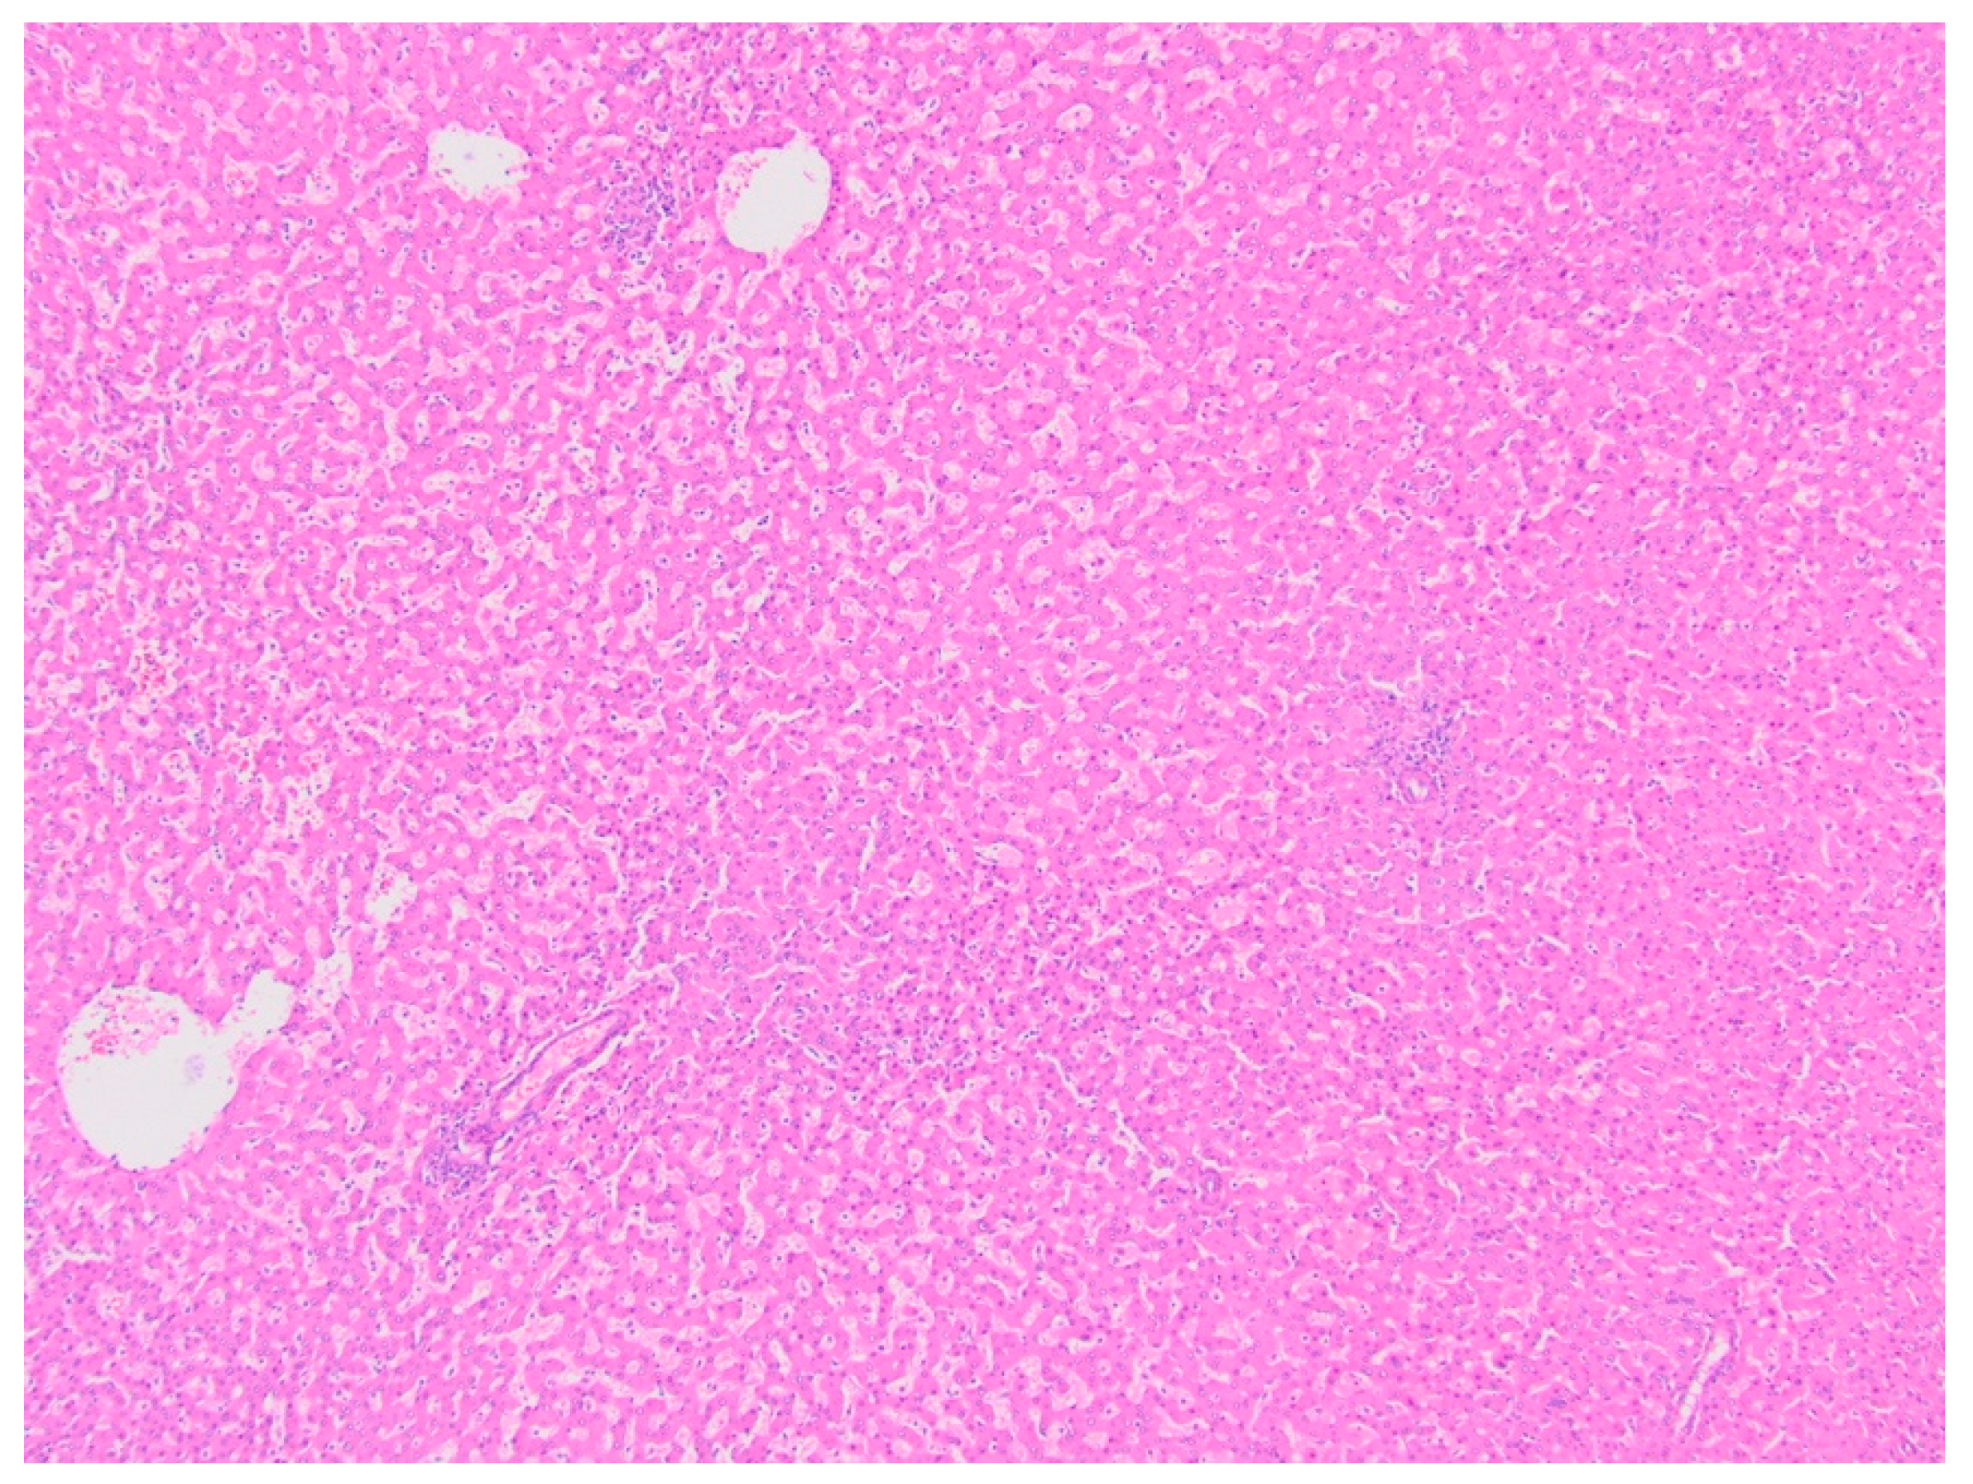

Histopathology and Immunohistochemistry